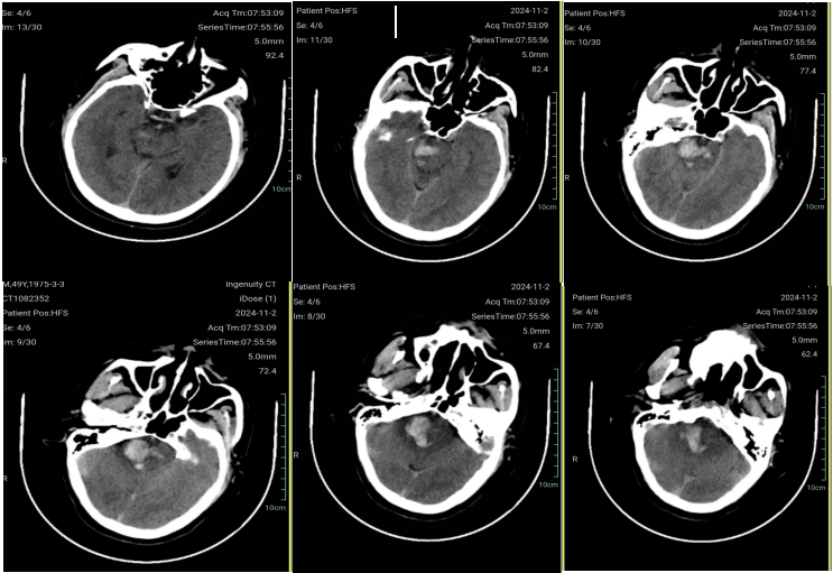

【“佟”话脑血运】佟志勇教授:大脑中动脉M1中段解离性动脉瘤的外科治疗策略

佟志勇

前天14:14